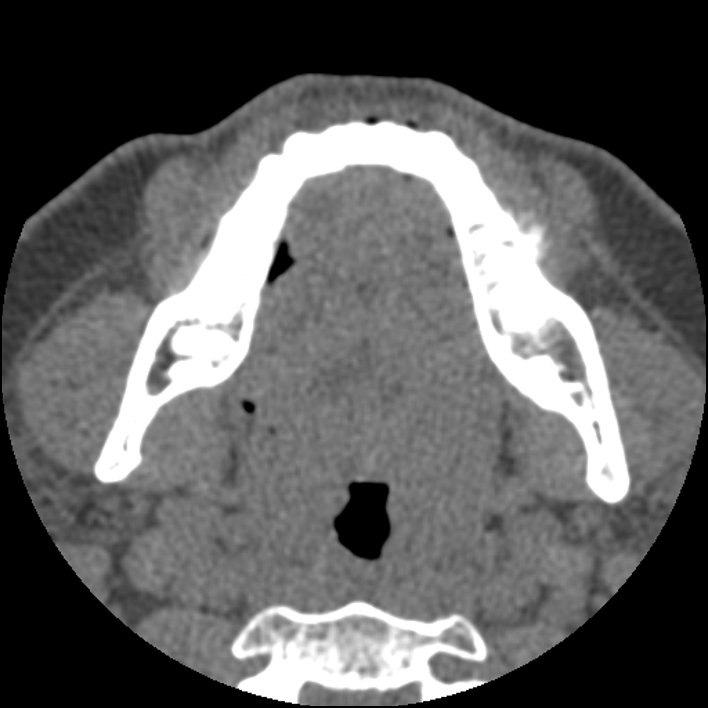

Figure 3 for case Chondroblastic osteosarcoma of the mandible

Figure 3